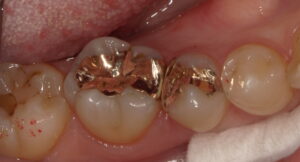

今回の患者さんは歯ぎしりの自覚があり、虫歯のなりにくさや詰め物の強度を考えてゴールドを選択されました。

装着後